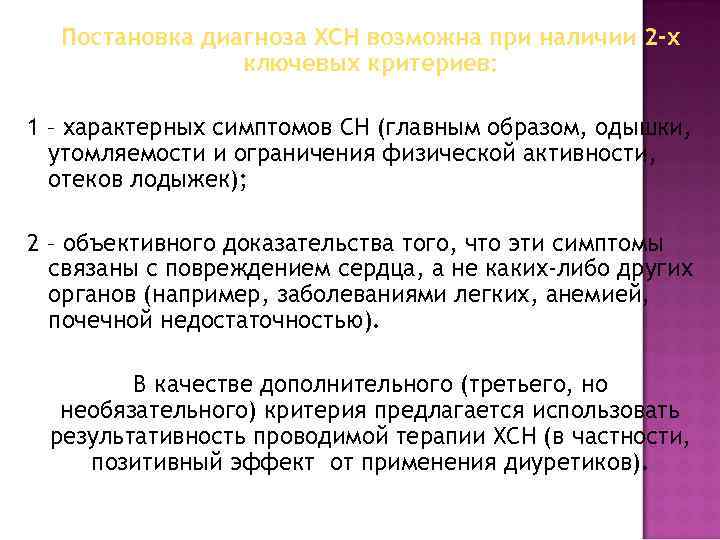

Постановка диагноза ХСН возможна при наличии 2 -х ключевых критериев: 1 – характерных симптомов СН (главным образом, одышки, утомляемости и ограничения физической активности, отеков лодыжек); 2 – объективного доказательства того, что эти симптомы связаны с повреждением сердца, а не каких-либо других органов (например, заболеваниями легких, анемией, почечной недостаточностью). В качестве дополнительного (третьего, но необязательного) критерия предлагается использовать результативность проводимой терапии ХСН (в частности, позитивный эффект от применения диуретиков).

Постановка диагноза ХСН возможна при наличии 2 -х ключевых критериев: 1 – характерных симптомов СН (главным образом, одышки, утомляемости и ограничения физической активности, отеков лодыжек); 2 – объективного доказательства того, что эти симптомы связаны с повреждением сердца, а не каких-либо других органов (например, заболеваниями легких, анемией, почечной недостаточностью). В качестве дополнительного (третьего, но необязательного) критерия предлагается использовать результативность проводимой терапии ХСН (в частности, позитивный эффект от применения диуретиков).